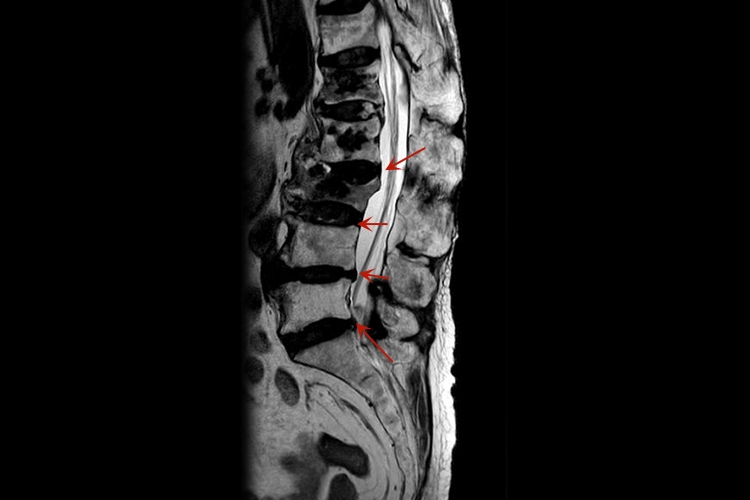

L3S1是指腰3-骶1,腰3-骶1椎间盘膨出患者通常不会有明显临床症状,个别患者会有神经根压迫症状,是腰椎间盘退变导致。

腰椎间盘膨出是指腰椎间盘高出椎管后方3mm,患者通常不会有明显的临床症状。但个别患者膨出于神经孔时,会有神经根压迫症状。